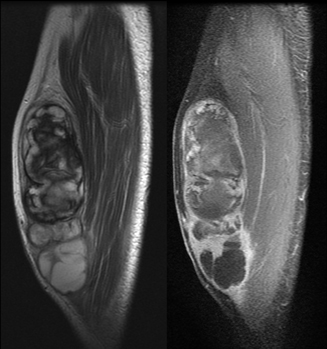

軟部腫瘍のMRI | 青木 隆敏, 青木 隆敏 |本 | 通販 | Amazon